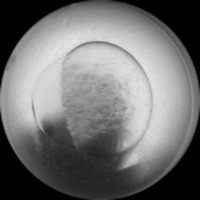

Research & Development: Researchers studying embryo development can use the AliDatabase to automate the process of identifying different stages of zeb1 cells. This can speed up research and reduce the possibility of human error in stage classification.

Medical Diagnosis: In fertility clinics or other medical settings, the AliDatabase can be utilized to identify and sort unfertilized or unhealthy zeb1 cells. This could help in diagnosing certain fertility issues and developing treatment plans.

Educational Tools: The model can be used as an educational tool for biology or medical students. By using AliDatabase, students can better understand the stages of zeb1 cell development and engage with interactive studying methods.

Pharmaceutical Testing: Companies developing drugs or treatments that impact cell growth could use AliDatabase to monitor how zeb1 cells respond at different stages to these drugs, aiding in efficacy and safety tests.

Quality Control in Lab Conditions: The model can be used to identify 'bad' or 'advanced' stages of zeb1 cells, indicating contamination or other issues in lab conditions, thereby assuring the quality of scientific experiments.